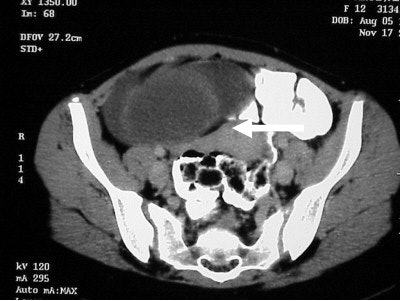

The image (Figure TC 2) demonstrates a contrast-filled bowel, the tip of the liver on the right, and a soft-tissue mass appearing at the level of the kidneys in the anterior portion of the abdomen.

![]() |

| Figure TC 3 |

| Figure TC 4 |

In figure TC 3 we can see a large soft-tissue mass measuring approximately 9 cm wide by 6 cm in AP diameter, and 14 cm in height. It contains both fluid and semi-solid components of soft tissue as well as assorted calcifications. The mass appears to terminate (Figure TC 4) just above the level of the uterus (arrow).